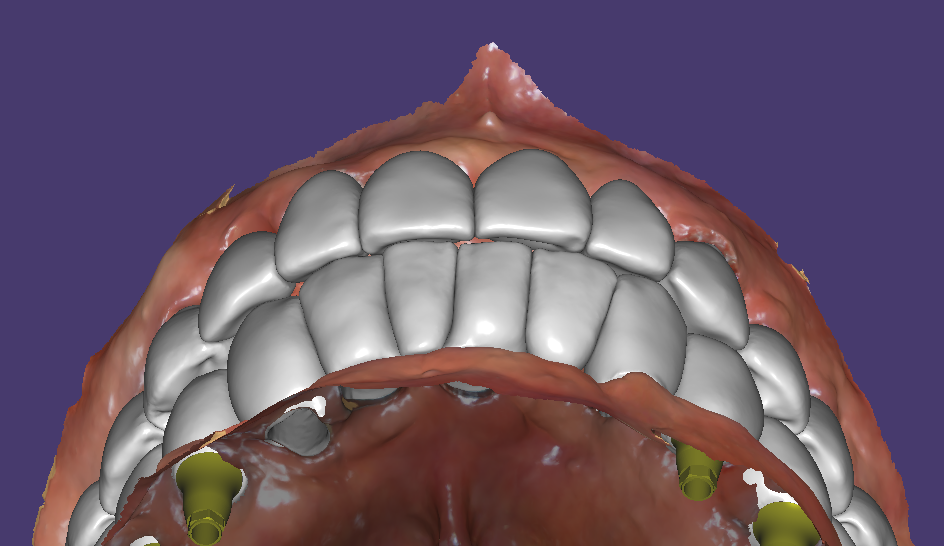

3개월후 스캔바디 스캔해서 최종보철 디자인

스캔바디를 끼우고 스캔을 하면 임플란트의 위치를 디자인프로그램에서 확인할 수 있어요. 거기에 맞게 맞춤지대주를 디자인하고 그 위에 지르코니아 보철디자인까지 한꺼번에 진행이 됩니다.

디자인이 모두 완료되면 바로 가공이 이루어집니다. 전체임플란트 보철의 디자인과 가공은 하루 정도가 걸립니다. 그래서 당일에 완료해서 끼우시는 것은 조금 어렵고 준비하신 다음날은 세팅이 가능합니다.

브릿지타입의 지르코니아 최종보철 세팅과정

이렇게 충분한 개수의 임플란트로 치료하면 원래 치아모양과 유사한 형태의 치아디자인이 가능합니다.